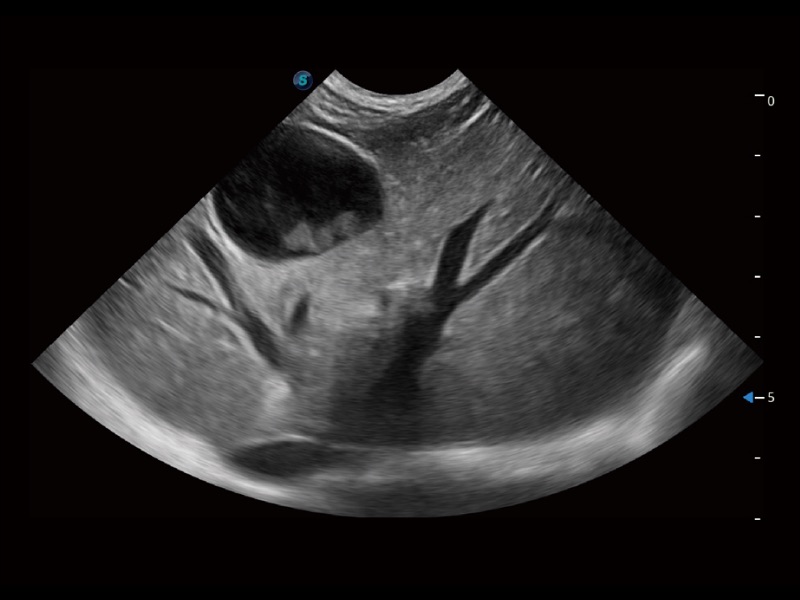

ProPet 70 进一步提升了微米成像算法,更加注重对基础原始图像的还原和保留,在有效减少斑点噪声、增强组织边界显示的同时,避免过度优化丟失真实的解剖信息。

增强穿刺针在动物解剖结构中的位置,提高穿刺介入的安全性和准确性。

ProPet 70专为动物医生设计,对不同的动物体型和生理结构作出了针对性的优化。通过动物影像专用软件,可满足个性化的应用需求,帮助动物医生获得更精确的诊断数据。

为精细结构及组织边缘提供高清晰度的图像和更大的成像视野。帮助减轻医生的用眼疲劳,快速精准获得测量的数据。